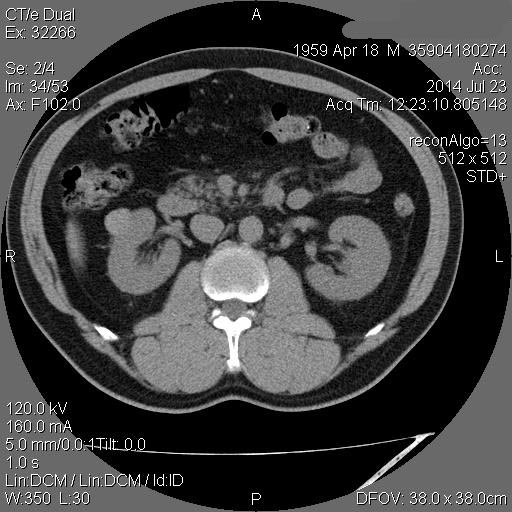

Образование в правой почке

Мужчина средних лет.Жалоб не предъявляет.

С его слов, 10 лет назад в правой почке находили кисту.

Рак - на первом месте. Показано КТ с контрастирванием.

Ответ каунасских радиологов - киста почки.

В том то и дело. Но тем не менее - это киста, анамнез уже несколько лет.besliu писал(а):Что-то на узи на кисту не похоже...

Динамики нет, на последнем видео четко видна киста при включенной 2й гармонике